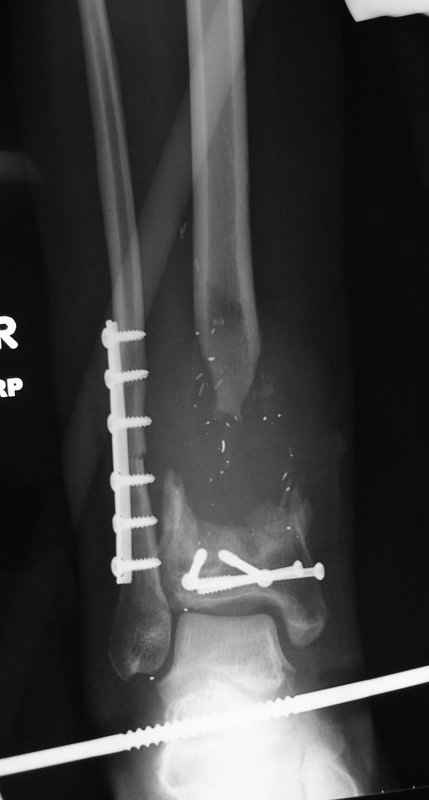

Пациент 19 лет, производственная травма, придавлен тяжелой плитой. Политравма (ISS 21).

1 - рентгенограмма (прошу прощения за качество) при поступлении;

Произведено ПХО, acute shortening (5 см), фиксация стержневым аппаратом Hoffman.

3,4 - через 4 недели наложен спице-стержневой аппарат, произведена остеотомия большеберцовой кости в верхней трети, раны зажили, проводилась дистракция в аппарате.

5, 6 - через 2,5 мес после травмы выполнен закрытый остеосинтез блокируемым штифтом.

7, 8, 9, 10, 11 - через 8 мес после травмы перелом сросся.